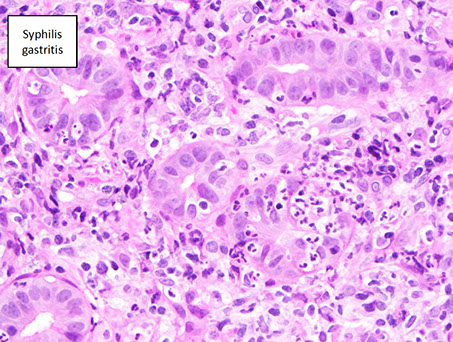

Infectious gastritis (syphilis, CMV, EBV)

Syphilis

- has a variable appearance, having lots of mixed inflam (similar to autoimmune pangastritis) c gastric gland damage; should do direct IF or immunolabeling if suspected